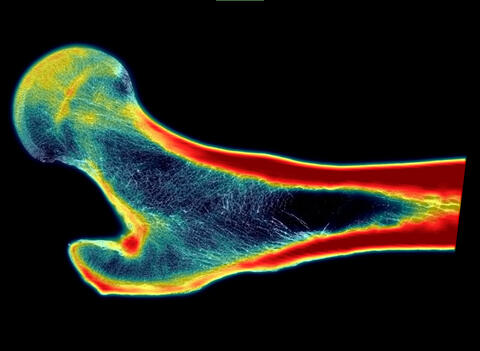

February 11, 2025 — Southwest Research Institute (SwRI) has developed new technology to enhance clinical bone imaging and decrease osteoporotic fractures in the elderly. The tool, described in a new SwRI-led study, uses artificial intelligence (AI) to create super-resolution images showing the inner structures of bones in great detail to better determine risk for fracture.

SwRI found that in almost all cases, the super-resolution (SR)-enhanced images were more accurate than X-rays or CT scans in quantifying bone characteristics that are indicative of strength and fracture risk.

For this study, SwRI used a type of AI known as super-resolution technology, a set of techniques used to make low-quality images sharper and more detailed. SwRI’s deep-learning SR approach trains AI to map complex patterns and textures by teaching it to observe details in several examples. As a result, it can use low-resolution image data of bones to predict what a much higher resolution image of that bone would look like.

Frazer suggested applying SR technology to medical imaging equipment, which would provide a clinician raw medical images, such as X-rays, as well as processed images enhanced by AI. The resulting images are sharper and clearer, potentially accompanied by additional diagnostics to help physicians make better medical decisions.